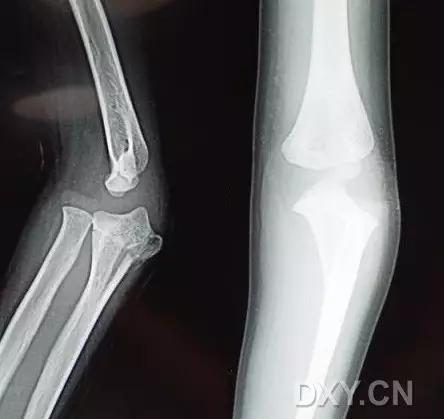

5. Hoffa 骨折

指股骨远端冠状面的骨折。

病例 1:一般股骨髁间、髁上粉碎骨折中含 Hoffa 骨折的不少见,但单纯后髁骨折则很少见。

正位片

侧位片

水平位 CT

第 2 例

第 3 例